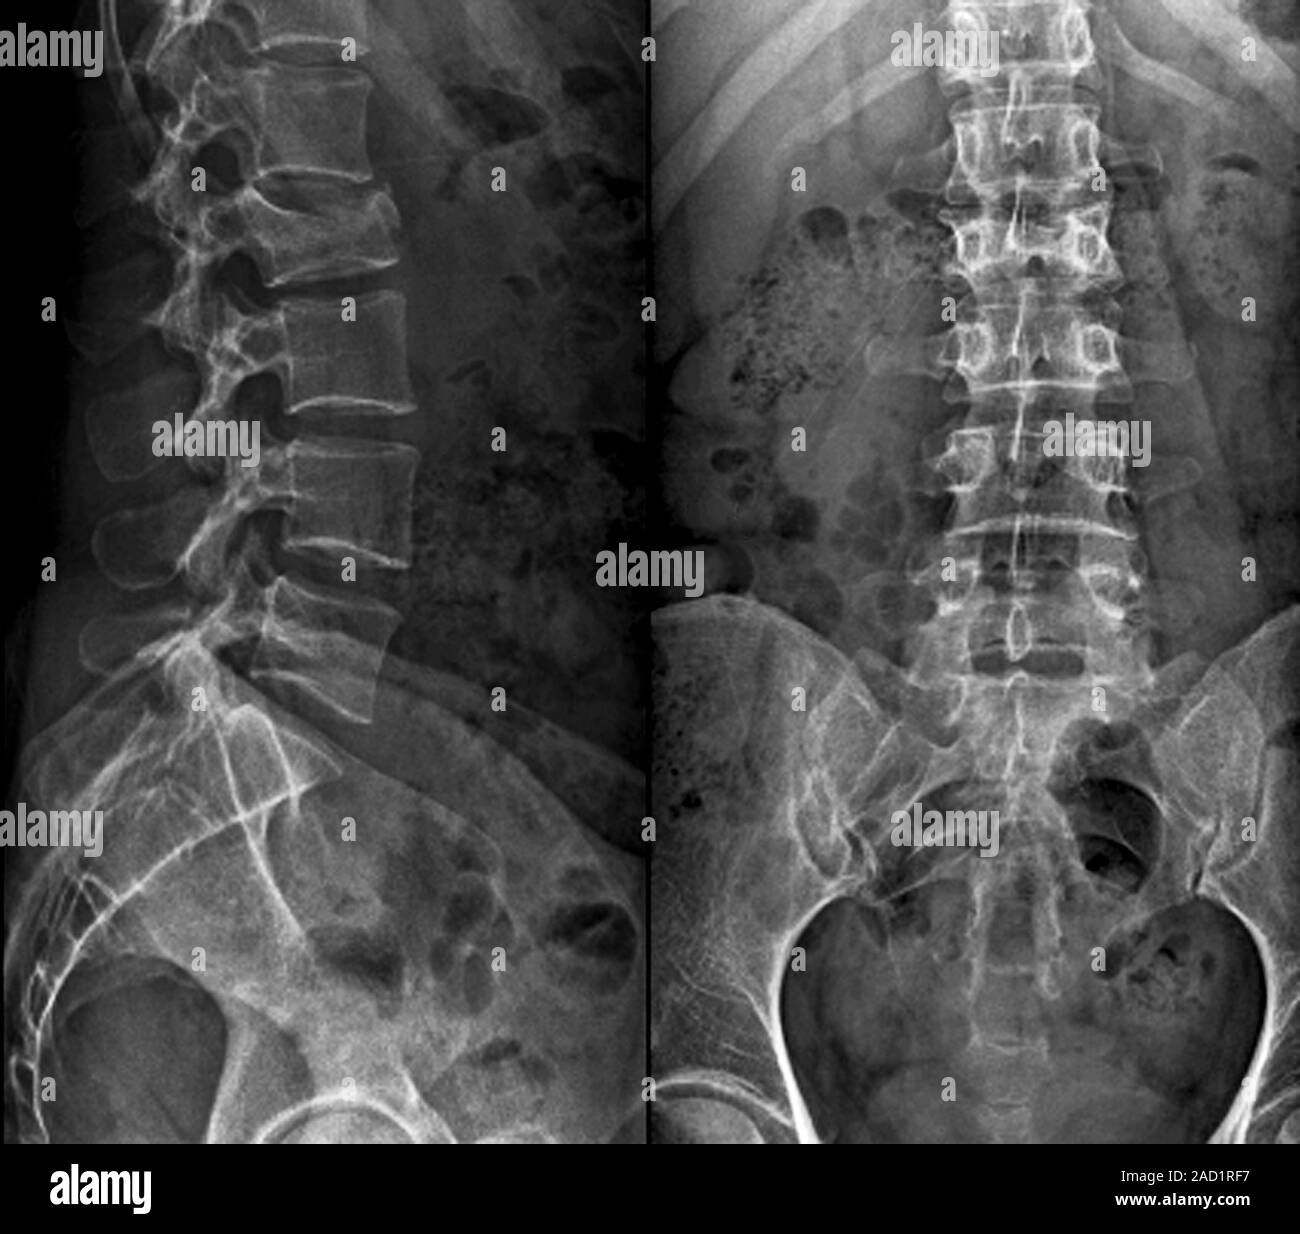

From wikem.org

Thoracic and lumbar compression fractures WikEM Compression Fracture Untreated A compression fracture is a type of broken bone that can cause your vertebrae to collapse, making them shorter. Compression fracture treatments can be surgical or nonsurgical, depending on the severity of the injury. A compression fracture typically occurs in the. A thoracic compression fracture is a serious medical condition that, if left untreated, can potentially. This often happens to. Compression Fracture Untreated.

From www.researchgate.net

Standing spinal Xrays shows a compression fracture of T7 vertebral Compression Fracture Untreated What happens when a thoracic spine compression fracture is left untreated? After a number of compression fractures, the shape of the spine can change. A thoracic compression fracture is a serious medical condition that, if left untreated, can potentially. Height loss can occur as the spine compresses and becomes shorter. Compression fracture treatments can be surgical or nonsurgical, depending on. Compression Fracture Untreated.